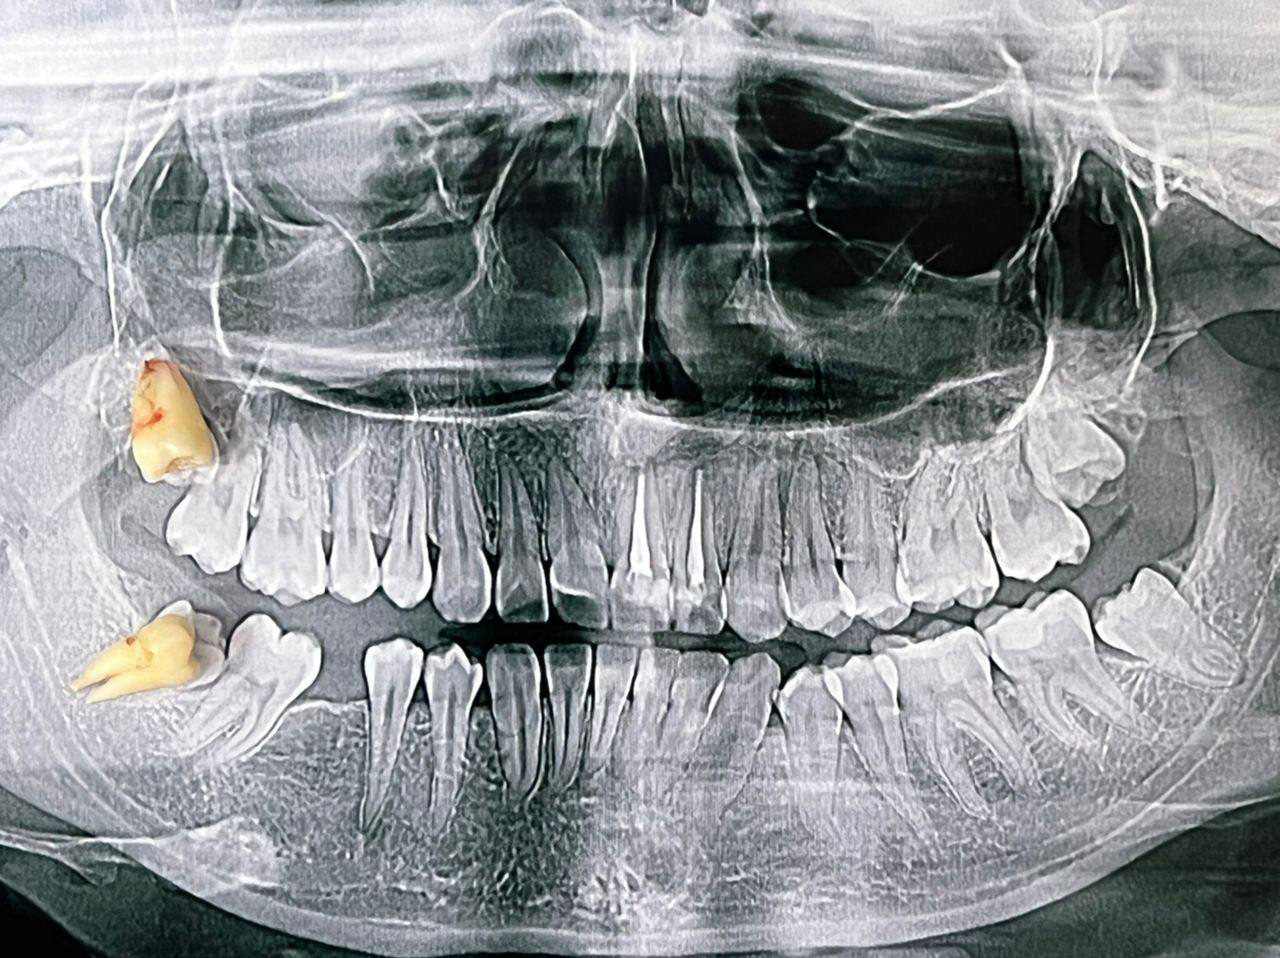

Атравматичное удаление зубов – наиболее безболезненная и щадящая процедура, которая практически не травмирует десну и костную ткань.

Зуб извлекается частями, что позволяет не травмировать окружающие ткани.

В нашей клинике осуществляется удаление самых сложных «зубов мудрости». Обычно удаление зуба под местной анестезией занимает от 10-15 минут, но иногда процедура может занять 30 или даже 60 минут и более.